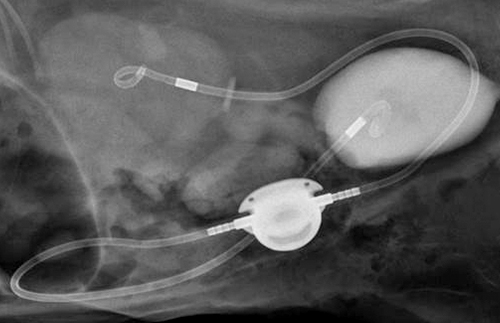

CT, 초음파, X-ray

고양이 영상의학센터

(Feline Imaging Center)

최첨단 영상장비를 통해 더욱 정확한 진단이 가능합니다.

비뇨기, 정형, 소화기 등

고양이 외과수술센터

(Feline Surgery Center)